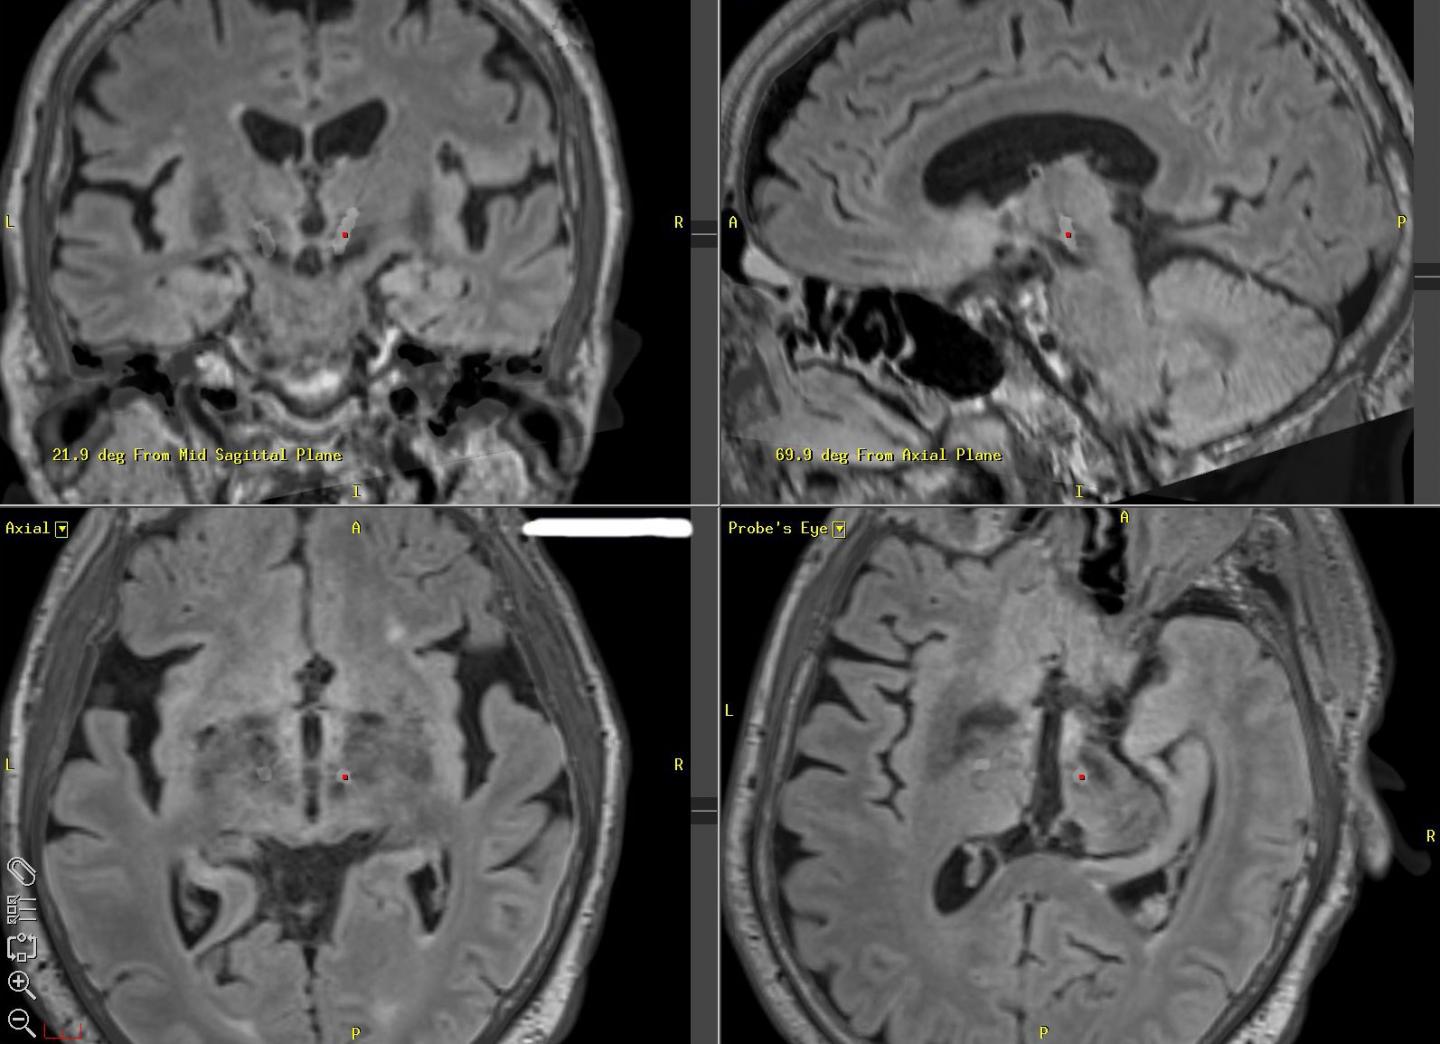

image: Magnetic resonance images show the location deep in the brain where neural stimulation is being applied to reduce this patient's tremors (red dot). New software to determine efficient, effective patterns for stimulation could extend the battery life of implants. view more

Credit: Duke University